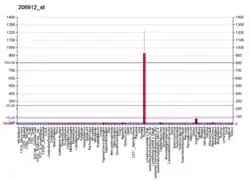

Tissue localization

FOXE1 is expressed transiently in the developing thyroid and the anterior pituitary gland.[9]